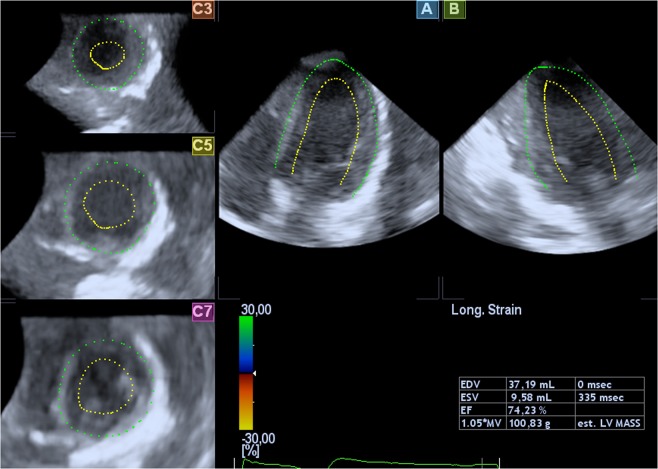

Figure 5.

Sample images of the heart by RT3DE (software Toshiba). Two-dimensional slices from a representative real-time 3D echocardiographic data set with endocardial (yellow) and epicardial (green) borders of the left ventricular myocardium.